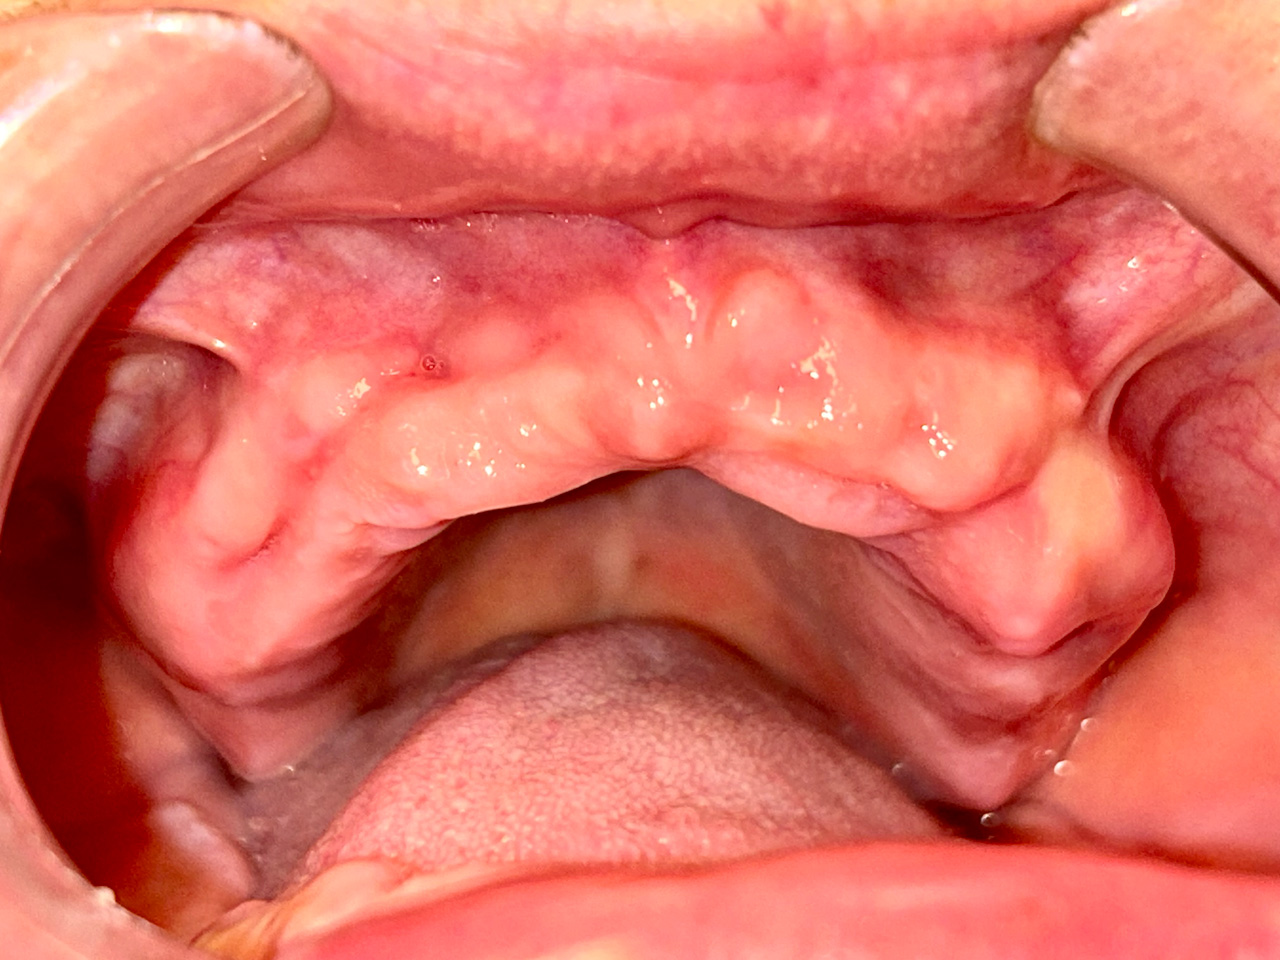

Elhanyagolt fogsor cseréje 2 nap alatt

2 nap alatt varázsoltuk ezt a szép esztétikus alsó, felső körhídat implantátumokkal megtámasztva a korábban elhanyagolt szájba. Az 1. nap 26 fogat távolítottunk el, mert annyira rossz állapotban voltak, és rögtön azonnal terhelhető IHDE svájci implantátumokat raktunk be, fentre 8, lentre 6 darabot. A sebeket összevarrtuk és intraorális szkennerrel digitális lenyomatot vettünk. 2 nap múlva pedig beragasztottuk a kész PMMA műanyag körhidakat. Dr. Kelemen Péter és a Symbion Fogtechnika munkája.